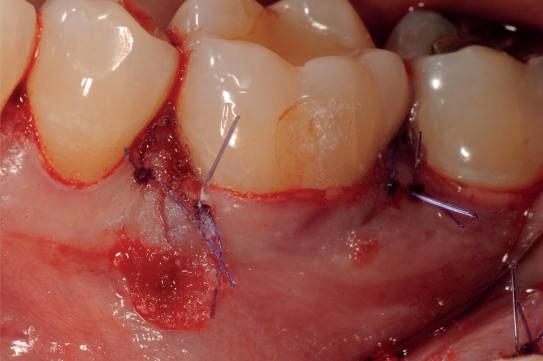

Examinarea parodontală a relevat sângerări generalizate la sondare și adâncimi de sondare de până la 9 mm la molarii maxilari și mandibulari, cu multiple furcații implicate la fiecare molar (fig. 2-7). Prezenta mobilitate multiplă de clasa I la dinții posteriori și de clasa II la dinții nr. 16 și 21 (molarul prim maxilar drept și incisivul central maxilar stâng).

2-4. Imagini înainte de tratament: lateral dreapta (fig. 2), frontal (fig. 3) și lateral stânga (fig. 4). Notă: Molarul prim maxilar drept (dintele 16) (fig. 2) ar fi identificat ca fiind molarul cel mai afectat parodontal care era planificat să fie menținut.

Figurile:

5, 6. Imagini ocluzale înainte de tratament: maxilar (fig. 5) și mandibulă (fig. 6).